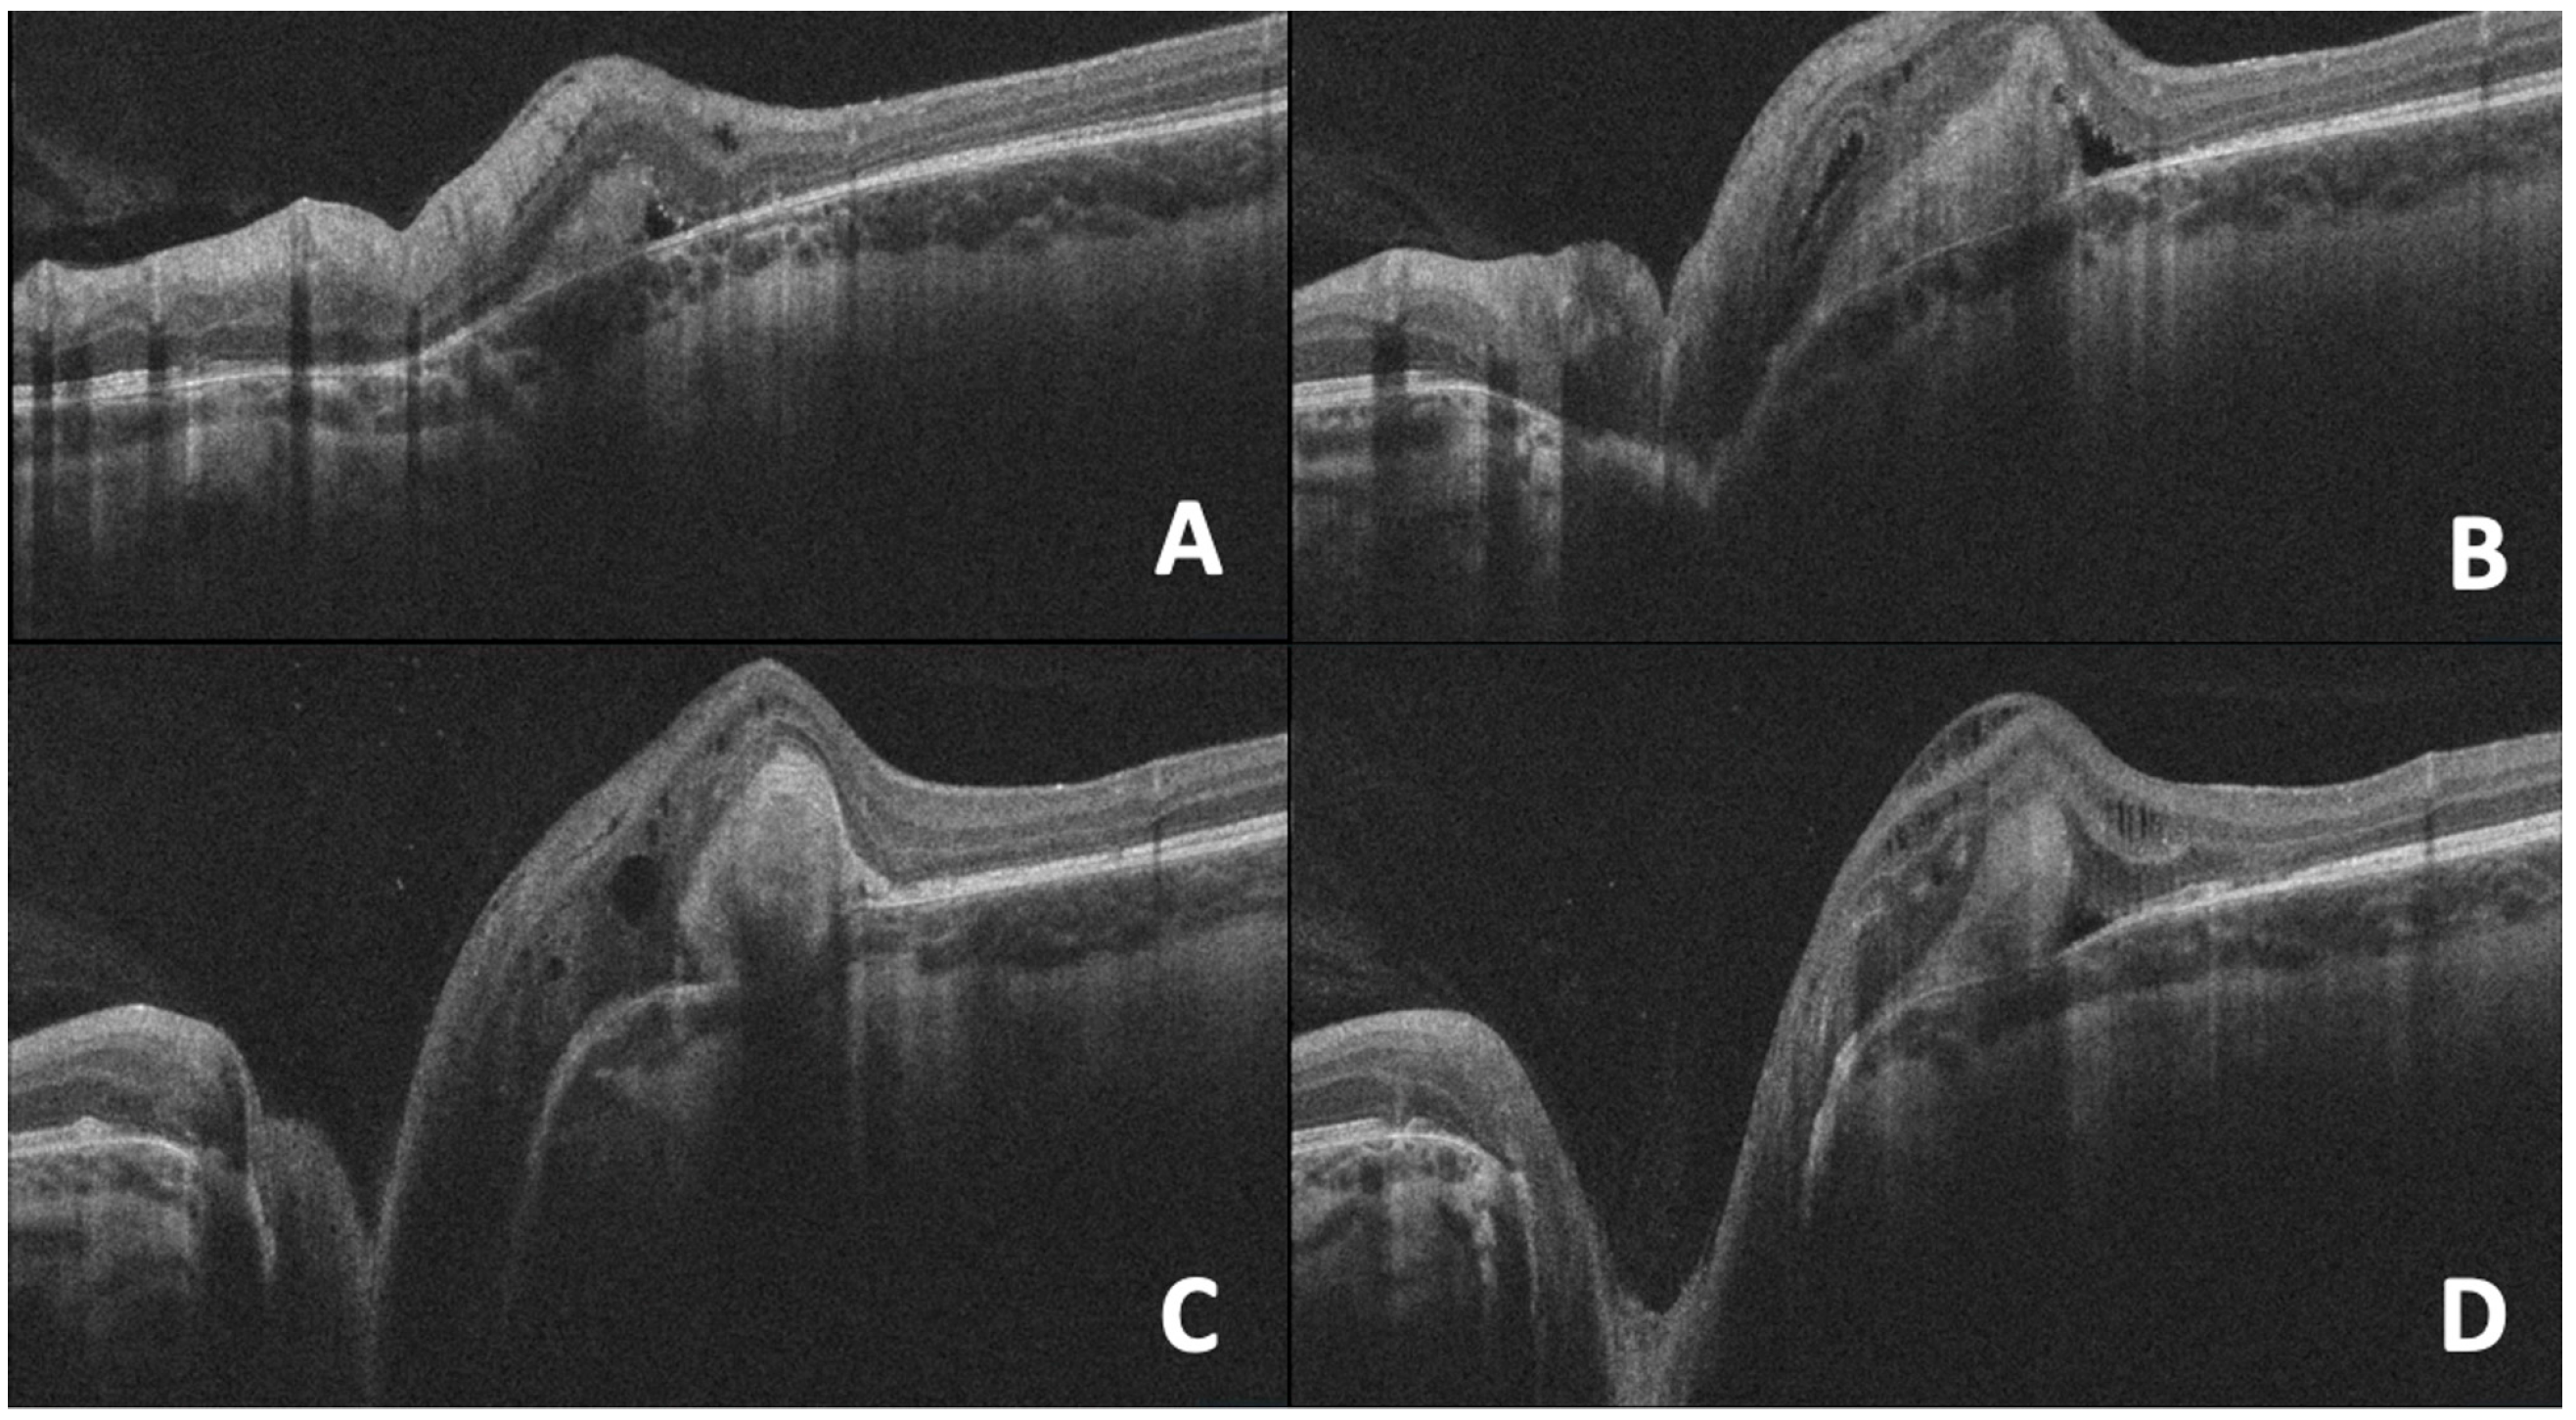

| 7. Optic Pit | Deep excavation of the optic disc with lamina cribrosa defect, herniation of nerve tissue, and associated serous macular detachment or intraretinal schisis. | Advanced OCT (EDI and SS-OCT) enables full visualization of pit morphology and fluid dynamics, improving diagnosis and monitoring of OP maculopathy. |